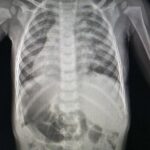

Марихуана и другие продукты из конопли, такие как гашиш, могут серьезно изменить сознание человека. Отказ от их употребления часто сопровождается симптомами абстиненции, такими как депрессия и раздражительность, что приравнивает их к более сильным наркотикам. Наше исследование показало, что курение марихуаны создает на легкие нагрузку в пять раз больше, чем обычный табак, и повышает риск развития раковых заболеваний. Более того, марихуана влияет на центры удовольствия в мозге, постепенно увеличивая зависимость и потребность в более сильных стимуляторах, что может привести к более серьезной наркозависимости.